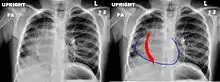

Le nom de ce syndrome vient de l'aspect angiographique du vaisseau anormal dont la forme, oblique en bas et en dedans, s'élargissant de haut en bas, évoque celle d'un cimeterre[3].